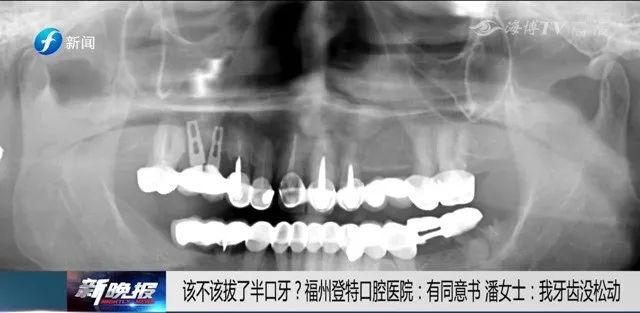

潘女士手机里保存着

她在其他医院拍的牙齿CT片

这个CT片显示她下牙的牙齿

大部分牙冠和牙根是完好的

潘女士:我牙齿没有松动综合治疗椅,牙片机,洁牙机。怎么都松动了?你怎么这么说?你可以把片子拿出来看执业助理医师,待遇优厚,底薪加提成